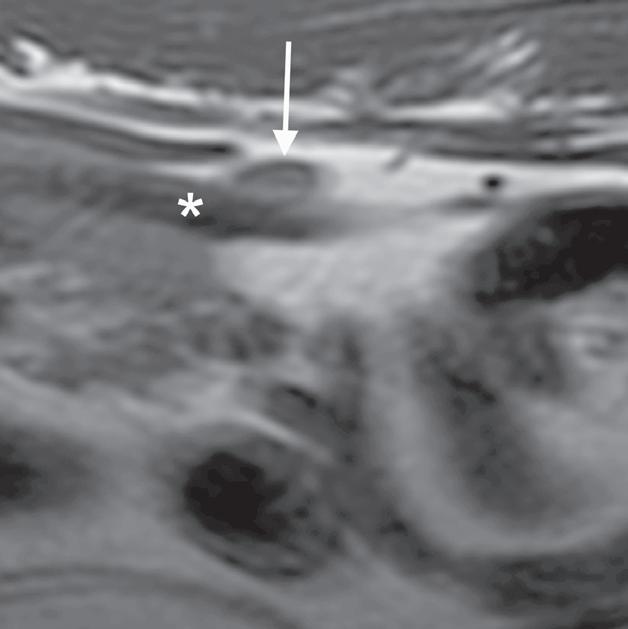

Rycina

3.2.8. Podwichnięcie kręgów szyjnych ze złamaniem wyrostka stawowego (pies) TK i MR

Badania wykonano u 5-letniej samicy mieszańca w typie teriera, która została pogryziona w okolicy szyjnej przez większego psa tego samego dnia, w którym wykonano badania. Podczas wizyty u psa zaobserwowano deficyty neurologiczne z neuroanatomiczną lokalizacją w obrębie C6–T2. Radiogramy przeglądowe ukazały grzbietowe podwichnięcie kręgu C7 względem C6 oraz zwężenie przestrzeni międzykręgowej C6–C7 (a – grot strzałki). Podobne zmiany uwidoczniono na obrazach TK w projekcji strzałkowej i 3D (b, f – grot strzałki). Dodatkowo stwierdzono wieloodłamowe złamanie z przemieszczeniem prawego doczaszkowego wyrostka stawowego kręgu C7 (c–e – strzałka). Dla porównania przedstawiono prawidłowy lewy wyrostek stawowy (f – strzałka). W badaniu MR przestrzeń międzykręgowa C6–C7 była zwężona i wykazywała obniżoną intensywność sygnału w obrazach T2-zależnych (i – strzałka), a przemieszczony materiał dyskowy znajdował się w prawej dobrzusznej części kanału kręgowego (g, h – grot strzałki). W obrazach występują cechy ucisku na rdzeń kręgowy (g–i) oraz zwiększona intensywność sygnału w sekwencji T2-zależnej w obrębie rdzenia na poziomie C6–C7 (h, i), co wskazuje na jego uszkodzenie wewnętrzne. Materiał dyskowy został chirurgicznie usunięty z kanału kręgowego, a podwichnięcie zredukowano i ustabilizowano operacyjnie